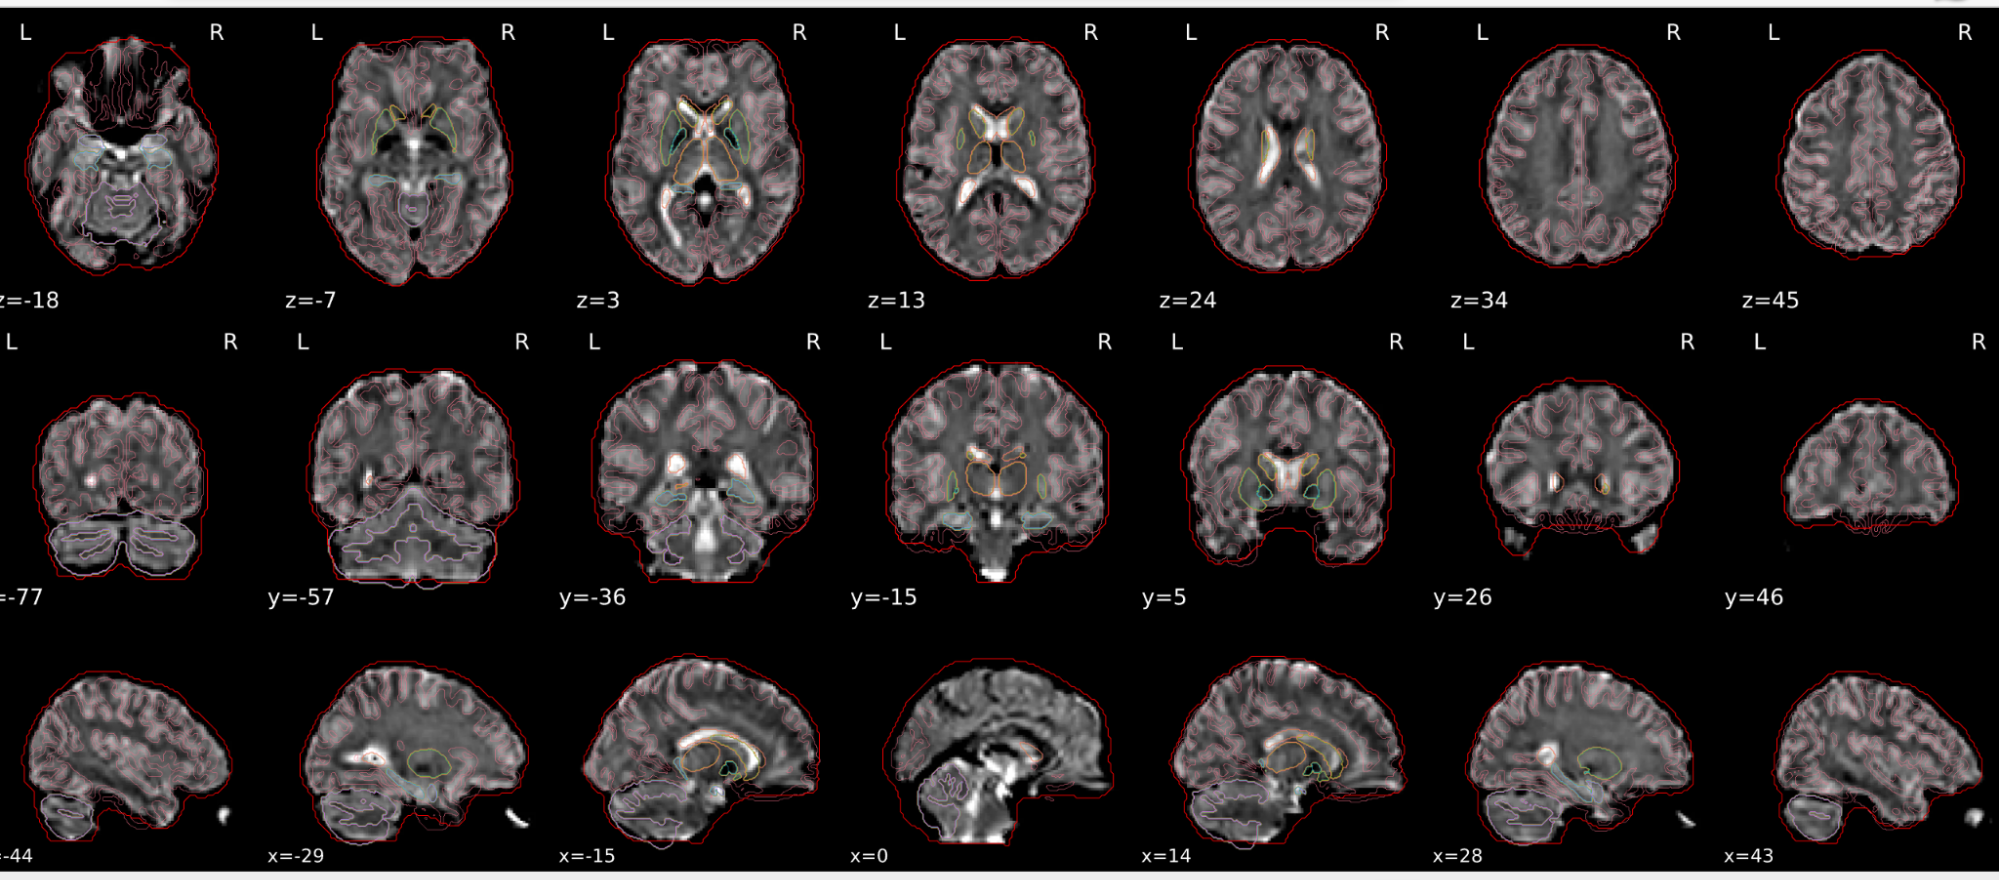

EPI spatial normalisation

This QC step shows the registration of the EPI image to MNI space.

Example of a good subject

- If the registration performed well, you should see an overlap (i.e., correspondence of structures) between the MNI template and the EPI registered to the MNI space.

- If parts of the brain are missing due to the scanner field of view, this is fine. For example, the cerebellum may be cut off for a participant with a large head.

Example of a bad subject

- In case of poor registration, you should see a misalignment of the EPI and the MNI template

Summary

| good | bad |

|---|---|

| Overlap (i.e. match of structures) between the MNI template and the EPI registered in the MNI space | Misalignment of the EPI and the MNI template |

| If parts of the brain are missing because the field of view of the scanner is limited, the EPI spatial normalisation does not have to be excluded e.g. cerebellum cut off in person with large head |

If parts of the brain are missing because the field of view of the scanner is limited, the EPI spatial normalisation does not have to be excluded (e.g. cerebellum cut off in person with large head)